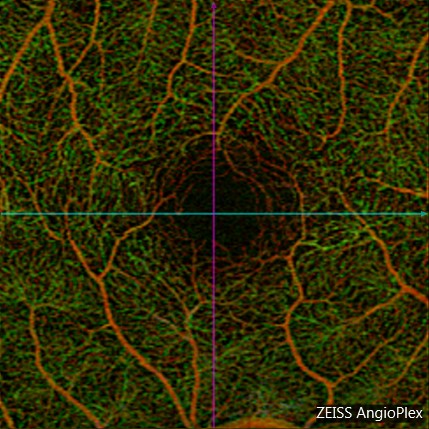

OCT is a modern imaging device that allows us to look at the macula with amazing details. This has allowed us to detect problems in the macula sooner and more accurately than ever before. And now added to this, there is a new technology called OCT Angiography, which allows us to detect abnormalities in the tiny blood vessels in the macula. Those tiny blood vessels, when they start to grow in an abnormal way, can lead to conditions like wet Age-Related Macular Degeneration (AMD). There are nowadays very effective treatments for wet AMD to stop these blood vessels from growing further, and so detecting the early stages of these blood vessel growth is very important. In addition to AMD, there are many other retinal conditions that are detectable by OCT Angiography. In diabetes mellitus, for example, OCT Angiography can detect early microscopic changes in blood vessels before there is any other sign of diabetic retinopathy. In those cases, this detection can help reinforce the diagnosis and increase the awareness among the diabetes care-providers, since what is happening to the eye is probably happening elsewhere in the body. OCT Angiography is a new, non-invasive, modern imaging device that will allow us to provide better care to our patients than ever before.

OCT Angiograophy shows ultra-high resolution of the macular blood vessels